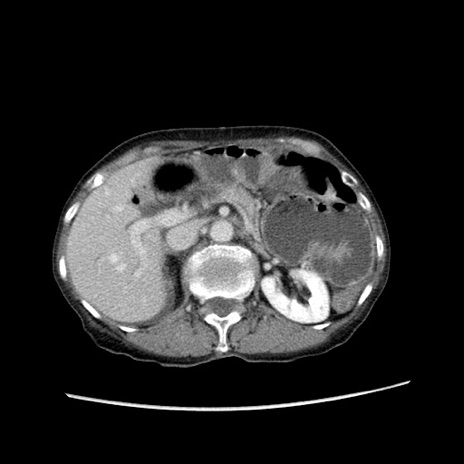

冠状断像

【症例】80歳代女性

【主訴】胸のつかえ感

【現病歴】約9時間前に食後から胸のつかえた感じあり、嘔吐あり、来院。

【既往歴】胃癌(全摘)、胆摘、虫垂炎

【身体所見】心窩部に圧痛あり、反跳痛なし。

【データ】WBC 5700、CRP 0.05